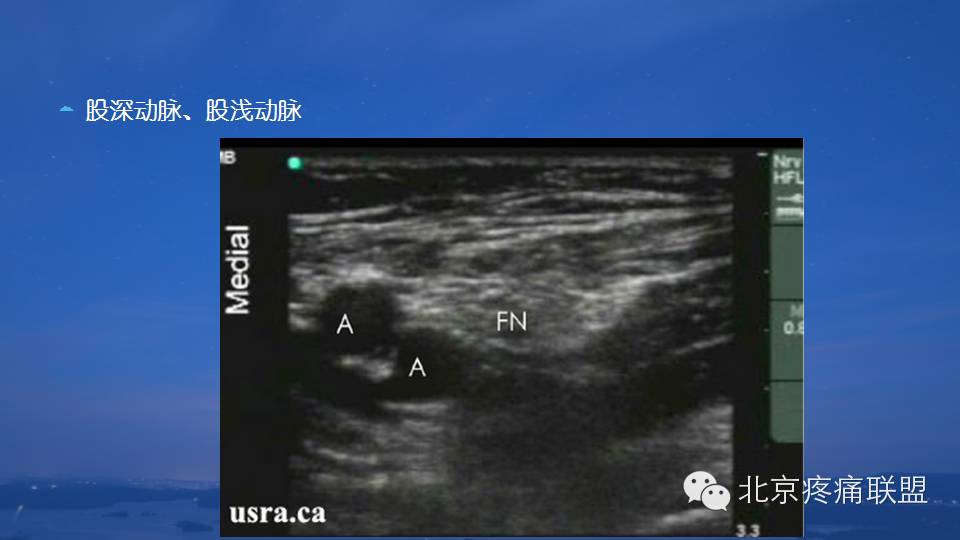

超声引导下股神经阻滞

图片尺寸960x540